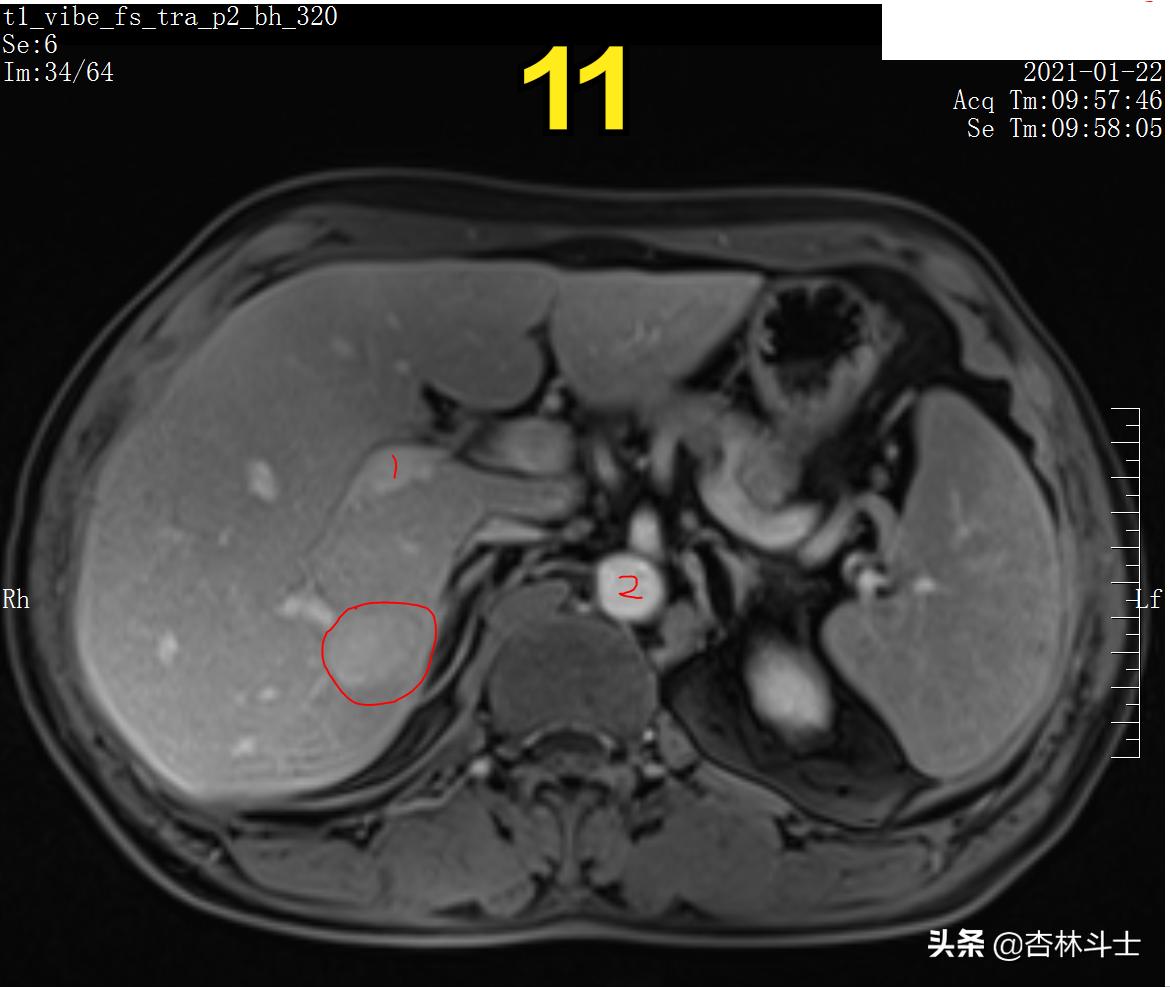

图11 T1压脂门静脉期

图10、11病灶相对肝脏实质呈高信号。 图11中 1、为肝门静脉右支 2、为腹主动脉。